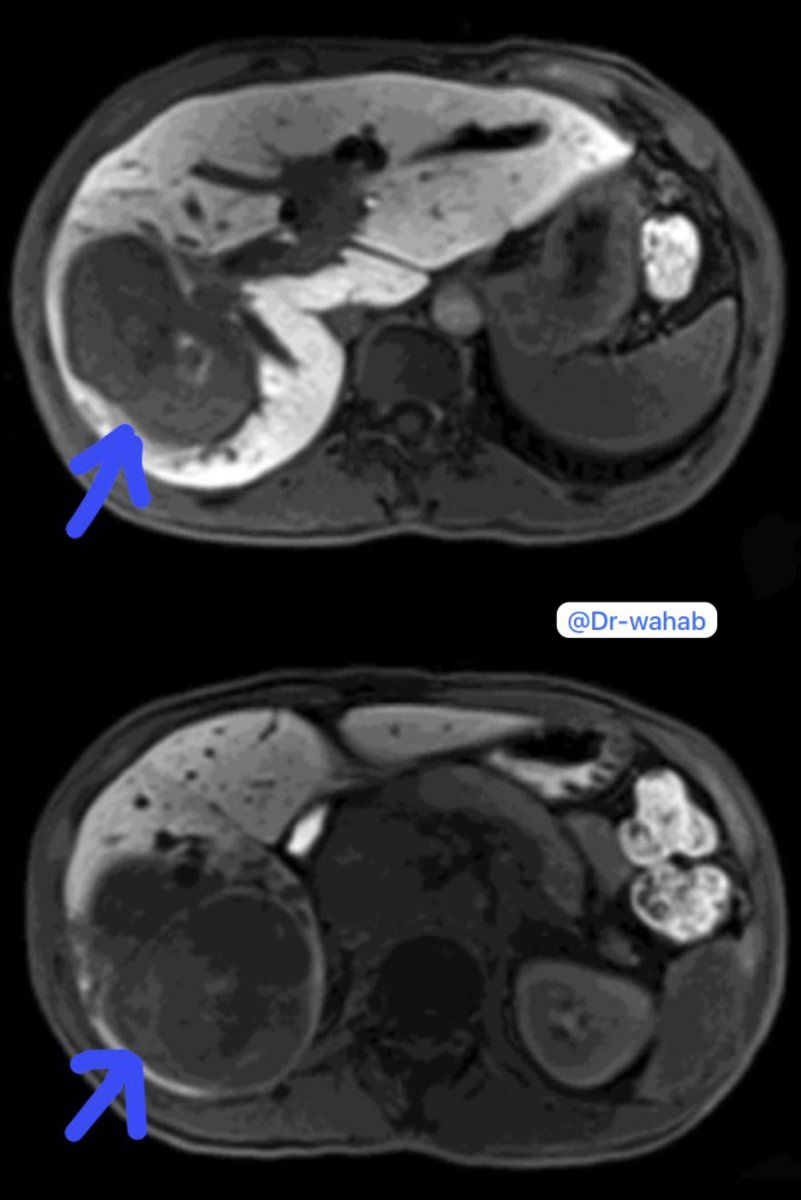

بفضل الله وتوفيقه .. أجرينا الإسبوع الماضي عملية متقدمة (بالمنظار) لإستئصال ورم سرطاني متقدم (بكامل الفص الأيمن من #الكبد ومتغلغل بالمرارة وملاصق للقولون الأيمن).

⬅️ سرطان القنوات الصفراوية / المرارية المتقدمة بالكبد

⬅️ Advanced Cholangiocarcinoma

⏺ لمريضه تبلغ من العمر ٥٠ عام،…

⏺ سرطان #القنوات_الصفراوية /المرارية داخل #الكبد:

هو نوع من سرطان القناة الصفراوية الناشئ من داخل الكبد (أي أن الورم يبدأ من القنوات الصفراوية / #المرارية داخل الكبد).